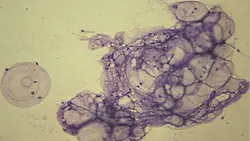

Question & AnswerQ • What types of inflammation cause cutaneous masses or lesions?A • Suppurative and pyogranulomatous inflammation are common causes of cutaneousmasses or open draining lesions. In aspirates where the primary process is suppurative inflammation, neutrophils are the most common cell type; they can be degenerative or nondegenerative. It is important to closely examine the nucleus of these cells for evidence of karyolysis—typified by a pale and swollen nucleus that has begun to lose its filamentous segments—because this is a hallmark feature of degenerative neutrophils. The presence of degenerative neutrophils is commonly associated with bacterial infection. Pyogranulomas consist of a mixed inflammatory population, including neutrophils, macrophages, multinucleated giant cells, and lesser numbers of lymphocytes and plasma cells. Infections with higher-order bacteria or fungi such as Blastomyces dermatitidis are a common cause of this type of inflammation (Figure 1, above).